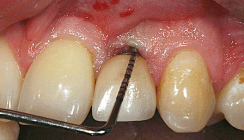

In einer prospektiven Studie wurden 46 Patienten aufgenommen (26 Männer, 20 Frauen), die jeweils einen nicht erhaltungsfähigen Zahn im Oberkieferfrontzahnbereich aufwiesen. Zur Bestimmung des gingivalen Biotyps wurden drei unterschiedliche Methoden angewandt und verglichen. Die rein visuelle Untersuchung, die visuelle Untersuchung unter Zuhilfenahme einer Parodontalsonde (PCP UNC 15 ST, Hu-Friedy) und die direkte Messung mittels spannungsfreiem Tasterzirkel (Dial Caliper N M/W, Aura-Dental). Nach der visuellen Bestimmung und nach der Untersuchung mittels Parodontalsonde wurde der gingivale Biotyp jeweils als dick oder dünn klassifiziert. Anschließend wurde der jeweilige Zahn extrahiert und eine direkte Messung mit dem Tasterzirkel durchgeführt. Die Messung wurde 2 mm apikal zum freien Gingivarand an dem mittigen fazialen Punkt vorgenommen. Die Messgenauigkeit betrug 0,1 mm. Der gingivale Biotyp galt als dünn, wenn die Messung 1,0 mm oder weniger ergab, und als dick, wenn die Messung mehr als 1,0 mm betrug. Die Untersuchungsergebnisse wurden mit einem McNemar-Test mit einem Signifikanzniveau von p = 0,05 verglichen. Es wurden 23 mittlere Schneidezähne, 15 laterale Schneidezähne und acht Eckzähne extrahiert und der gingivale Biotyp untersucht. In 25 Fällen war eine parodontale Vorschädigung der Extraktionsgrund. In 18 Fällen lag eine Zahnfraktur vor und in drei Fällen war ein endodontisches Versagen des Zahnes der Grund für die Extraktion.